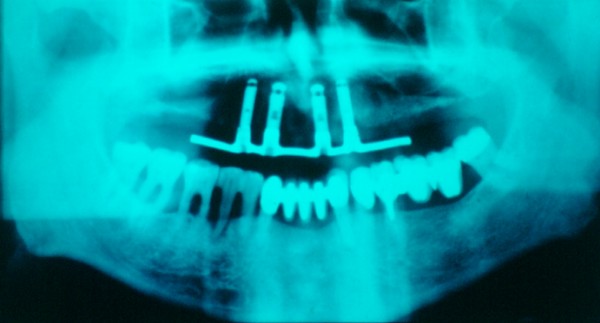

RESUMEN Más allá en el tiempo, respecto de las razones más frecuentes de fracasos como temperatura de fresado, infecciones, falta de fijación inicial, falta de higiene, etc., la OCLUSIÓN recibe sobre sí, la responsabilidad de la permanencia de la osteointegración, como así de la ortofunción del sistema todo. Sometimes ago,conserning the most frecuent reason of failures such as the strawberry action temperature, infections and lack of hygiene…etc.,the OCLUSION has itself the responsability af having the osteointegration well as the allsistem ortofunction . DESARROLLO La valoración de los fracasos en IMPLANTOLOGÍA es difícil de contabilizar sobre todo después del año, ya que el confort logrado por lo general, hace que el paciente realice correctamente sus primeros controles, y después; apoyado en su bienestar; intente subconscientemente olvidar ese período de su vida, que si bien le devolvió su capacidad masticatoria, fonética, social, etc., le ocasionara gastos, molestias, sufrimientos. … la APLICACIÓN de dichas fuerzas, requiere de una exactitud mucho mayor. Los esquemas propuestos a través de los años, no son muchos ni muy variados… I-Evitar las fuerzas tangenciales. II-Repartir las fuerzas lo máximo posible. Sin embargo, muchas veces se confunden los conceptos anteriores con criterios inexactos. Por ej: a-Reducción de las caras vestibulares y palatinas, aceptando que la menor superficie de intercontactos reduce la carga. b-Utilización de la Función de Grupo Posterior, en la creencia de que repartiendo el esfuerzo en las piezas posteriores, ganamos resistencia; a la potencia ejercida por los músculos. c-No permitiendo el contacto excéntrico de un canino implantado, para aliviarlo de las cargas laterales, sobre cargando de esta manera la tabla premolar-molar en el Lado de Trabajo. Algunos conceptos aislados, que forman parte de toda una filosofía de la Oclusión (OCLUSIÓN ORGÁNICA), sean tal vez de ayuda para echar luz sobre los preceptos anteriores. 1º-PROPORCIONES FUNCIONALES DE UN PAR OCLUSAL En la figura siguiente, observamos la relación final masticatoria de un PAR OCLUSAL: En el se ven los contactos puntiformes, producto del choque de superficies redondeadas contra superficies redondeadas («Solo pueden encontrarse en un punto» Ref: Principios Mecánicos Esferoidales.W.Mc.Horris.) Si Miramos con atención este tipo de contactos interoclusales, veremos que la superficie actuante es mucho menor que la superficie total de la cara oclusal: 45% (Fig.1) Por lo tanto, si no es por razones del Pilar de Emergencia para no crear un espacio biológico inadecuado… ¿POR QUÉ REDUCIR LA CARA OCLUSAL VESTÍBULO LINGUALMENTE? (Figs. 2-3-4-5) Si observamos con atención las figuras 2-3-4-5, veremos desde todos los planos , que el área contactante es muy reducida respecto del ancho oclusal total, siendo las fuerzas resultantes , AXIALES al eje implantario. 2º-FUNCIÓN DE GRUPO POSTERIOR. FUNCIÓN CANINA. Tres son las razones por las cuales nos inclinamos a la utilización de la Función Canina. En cambio, en el esquema de FUNCIÓN CANINA, podemos observar que el BRAZO DE POTENCIA, es prácticamente igual al de RESISTENCIA, equilibrando de esta manera la palanca y destruyendo mucho menos las estructuras de soporte(Interface I-H) (Fig. 7) Otra de las razones de peso en este tema es la DIFERENCIA DE ANGULACIÓN que existe entre la cara palatina del canino y las vertientes contactantes del sector premolar-molar. A MAYOR ANGULACIÓN, MENORES FUERZAS LATERALES(Perpendiculares al Plano), y por lo tanto , menor destrucción de la interface Hueso-Implante(Figs. 9-11). DIFERENCIAS EXCITATORIAS DE LOS GRUPOS MUSCULARES. Por último debemos considerar que el intercontacto dentario del sector anterior, estimula excitatoriamente a las fibras anteriores y verticales del temporal (Figs.12-13-14-15), mientras que los contactos posteriores lo hacen con la cincha pterigo-maseterina(Fig. 16-17-18-19) Por lo tanto ,si se comprende el fisiologismo de estos conceptos, es sencillo entender que la sobrecarga de los sectores posteriores es nocivo generando fuerzas tangenciales de Alto Potencial Patológico. 3º-FUNCIÓN DE GRUPO ANTERIOR Las ventajas de un Brazo de Resistencia mayor se acentúan cuando tenemos el esquema de FUNCIÓN DE GRUPO ANTERIOR. Además, debemos tener en cuenta que, durante la función de un Ciclo Masticatorio, es más importante la Desoclusión Final que la Desoclusión Inicial, ya que al ser más larga esta última, es durante el transcurso de su deslizamiento cuando se ejercen fuerzas laterales mayores(Fig. 21) A medida que la punta del canino inferior se acerca a la O.R.C., o sea al Punto de Contacto Intercanino, las fuerzas laterales disminuyen en virtud del acortamiento del brazo de potencia de la palanca, hasta que, al terminar su recorrido, la fuerza es proyectada axialmente sobre el eje del canino superior, debido a que, al margen de la intensidad que la fuerza trae durante el cierre, la dirección de la misma «apunta» en esa dirección. Por eso decimos que los caninos Axializan el Ciclo Masticatorio. Si estamos imitando en lo posible a la naturaleza, no olvidemos este detalle que los dientes naturales provéen, para evitar las fuerzas laterales del canino a la hora de realizar la supraestructura coronaria del mismo. Es ahora menester acentuar que la problemática concreta se manifiesta, no durante la función, sino durante la PARAFUNCIÓN… Cuando estudiamos recorridos de la Dinámica Mandibular, desde el conocido Bicuspoide de Posselt hasta cualquiera de los registros pantográficos, estamos invirtiendo la dirección del movimiento… A.- El primer premolar es el más anterior de la tabla oclusal posterior. Por lo tanto el brazo de resistencia es el mayor de dicha tabla. B.- El lateral, como parte del grupo anterior, cuenta con un empotramiento tipo «clavo largo», y el interseptum lateral -canino, que se opone a la fuerza, es mucho más grueso que la tabla vestibular del primer premolar(Fig.23) C.- Condiciones, las dos anteriores que se favorecen considerablemente, si al enfundar el lateral se logra junto al central una Función de Grupo Anterior. D.- De manera más artificiosa, la instalación de una placa de relajación, soluciona durante la noche lo nocivo de las fuerzas laterales. Veamos un par de casos, como ejemplo de lo dicho: Paciente de 54 años que se presenta a la consulta portando prótesis completa superior y antagonista natural que soporta fundas de porcelana. Obsérvese la función de grupo posterior ejercida, y las consecuencias de la misma: Otro paciente que presenta fractura de la cúspide fundamental de un onlay de porcelana antagonista de cinco piezas implantadas (Fig.27). Radiográficamente se observa la desinserción de uno de sus abuttments cementados (Fig.28). En el Lado de Trabajo (LT), no existe el canino encargado de desocluir la zona afectada (Figs.29-30) Como corolario, cabe entonces una pregunta: ¿Es el Implante en el canino quien debe preservar de patología oclusal al resto del sistema…. ¿Es el Implante…un medio…o un fín? BIBLIOGRAFÍA 1- Dibujos tomados del libro del mismo autor: «OCLUSIÓN ORGÁNICA… UN CAMINO HACIA LA REHABILITACIÓN ORAL»(en preparación) 2- «NEUROFISIOLOGÍA DE LA OCLUSIÓN» 3- «OCLUSIÓN Y FUNCIÓN» 4- «FUNDAMENTOS, TÉCNICAS Y CLÍNICA EN REHABILITACIÓN BUCAL» 5- «OCLUSIÓN Y REHABILITACIÓN» 6- «DISFUNCIÓN TEMPOROMANDIBULAR» 7- «PROCEDIMIENTOS CLÍNICOS Y DE LABORATORIO DE OCLUSIÓN ORGÁNICA» 8- «ESTUDIO ELECTRÓNICO DEL MOVIMIENTO MANDIBULAR» 9- «OCLUSIÓN: CONCEPTO PARA EL CLÍNICO» 10- «IMPLANTOLOGÍA CONTEMPORÁNEA» 11- «OCLUSIÓN Y DIAGNÓSTICO EN REHABILITACIÓN ORAL» 12- «PRINCIPIOS DE OCLUSIÓN»

Se queja de inflamación en el área implantada y movilidad en su prótesis. Se observa tumefacción gingival en la zona del Implante derecho.

Radiográficamente se observa una barra sumamente extensa sobre cuatro implantes, la que ejerce un brazo de palanca excesivo (Fig.24).

Erosiones desmedidas a nivel de las piezas posteriores (fig.25), pérdida de un implante distal y el corte necesario del brazo distal de la barra (Fig.26).

Las razones:

Se produce una evidente Función de Grupo Posterior, provocando fuerzas laterales en el Lado de no Trabajo(LnT), siendo estas las INTERFERENCIAS MÁS DELETÉREAS que puede provocar este esquema oclusal, destruyendo las estructuras de ese lado(LnT).